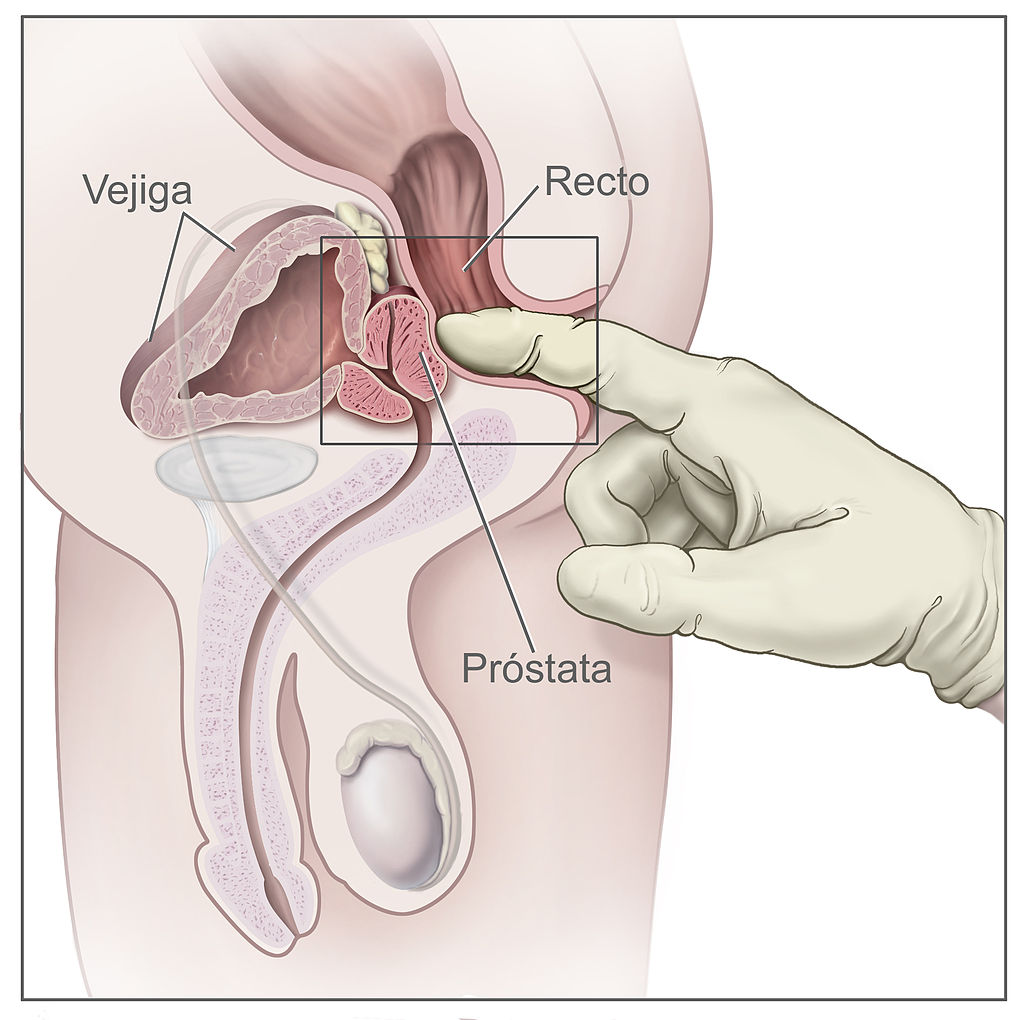

El Punto P, conocido como la próstata, es una glándula masculina que puede generar orgasmos intensos cuando se estimula adecuadamente.

¿Dónde se encuentra el Punto P? La clave está en la próstata, una glándula situada unos centímetros dentro del ano.

El Punto P se encuentra en la próstata masculina, una glándula del tamaño de una nuez ubicada justo detrás de la pared anal, en dirección al ombligo.

Está a pocos centímetros del esfínter anal, accesible mediante una exploración cuidadosa y delicada.

- Ubicación precisa: La próstata es una pequeña protuberancia que puedes sentir al tocar suavemente la pared anterior del recto.

- La sensibilidad es clave: La próstata es extremadamente sensible, por lo que un enfoque cuidadoso será clave para garantizar comodidad y placer.

“Estás buscando una bolita de carne del tamaño de una nuez que se esconde detrás de la pared anal. Encontrarla es como jugar a las escondidas usando tus dedos en lugar de tus ojos.”

La estimulación prostática se refiere al masaje de la próstata, una glándula del tamaño de una nuez ubicada justo detrás del pene y dentro del cuerpo, cerca del recto.

El Punto P (también conocido como punto G masculino) se encuentra dentro de la próstata, que está situada a unos pocos centímetros dentro del recto, justo detrás de la pared anterior.

- Técnica: Inserta un dedo o un juguete de manera suave en el ano y localiza la próstata a unos pocos centímetros dentro, hacia el ombligo. La próstata tiene una textura ligeramente más firme que los tejidos circundantes, y podrás sentirla si presionas ligeramente con movimientos suaves.